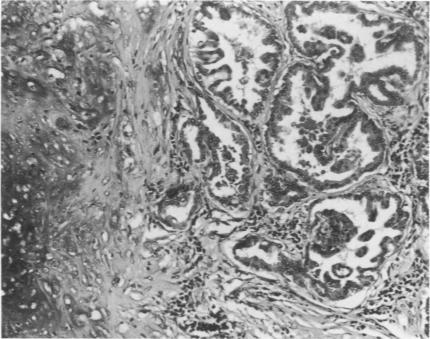

Animal model of human disease: canine mammary neoplasia.

Am J Pathol. 1974 Apr;75(1):225-8.

Abstract